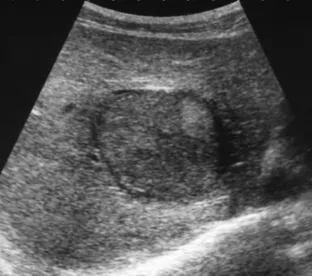

肝腺瘤

● 定义:是一种少见的肝脏良性上皮肿瘤,好发于育龄期女性。

● 超声表现

(1)呈圆形或椭圆形,轮廓较规则的结节或肿块回声,边界:清晰、光滑整齐。

(2)回声多变,可低可中可高,可均质可不均质,多为均质高回声。

(3)肝内出现较大的囊性包块,囊壁厚,境界清晰,内为无回声区,有分隔,分隔厚薄不均。

(4)内壁不整齐,有乳头状强回声,有后壁和后方回声增强效应。

(5)CDFI:病变周围血流丰富,有时较粗大,低阻。